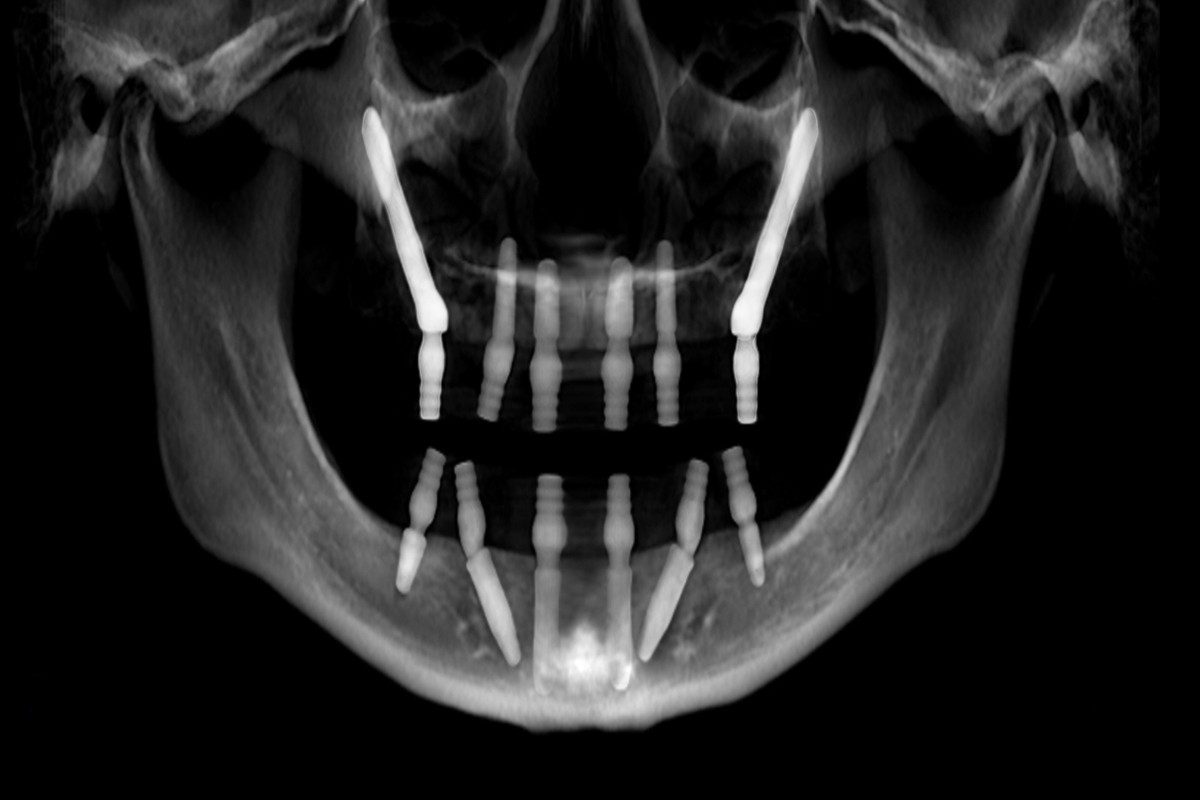

Next, a bone density evaluation will help determine the health of your jawbone. This usually involves imaging techniques like X-rays or a CT scan. These images provide a detailed view of the bone structure, helping your dentist gauge if there’s enough bone to support an implant. If bone loss is detected, don’t worry; there are ways to enhance bone density before proceeding.

For more extreme cases of bone loss, zygomatic implants might be the solution. These implants anchor into the cheekbone rather than the jawbone. This can be a game-changer for patients who have lost significant jawbone since they provide a stable foundation for dentures or crowns, even when traditional options aren’t viable.